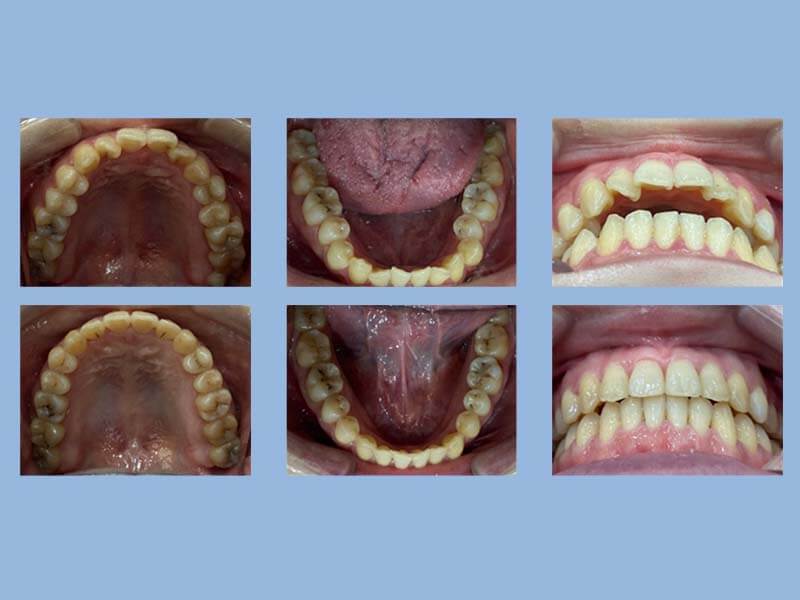

王先生 (22歲) 矯正完成

狀態 : 暴牙、擠、沒拔牙